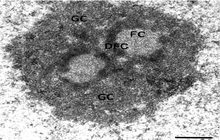

- Preparation of tissue sections for examination with a TEM microscope